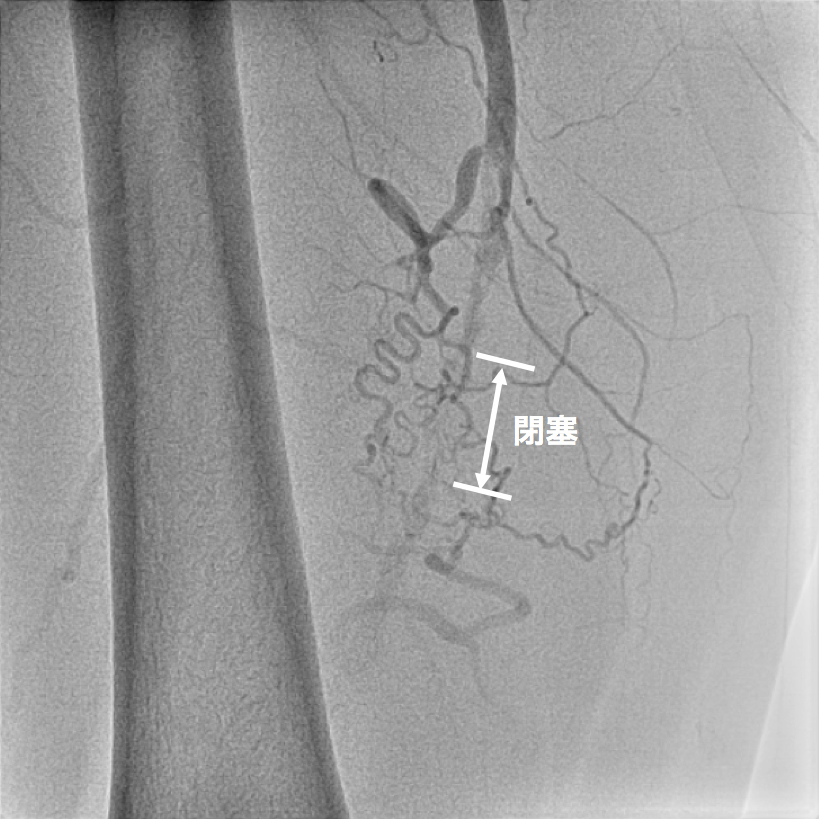

図4

サブトラクションという画像の処理を行うと、血流が途絶えており、血管が完全に閉塞していることがわかります。

図5

カテーテルによる血管造影検査ですが、CT検査

同様に閉塞していることがわかります。